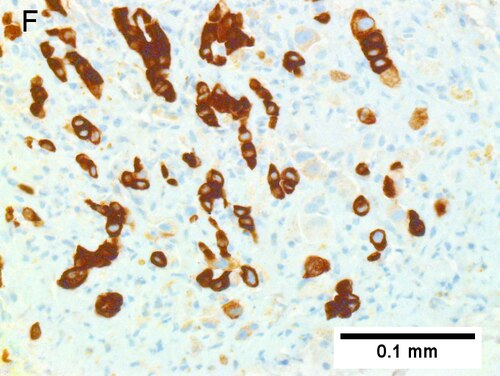

Cholangiocarcinoma, intrahepatic, with associated abscess. A. Aberrant spaces (arrows) contrast with the scar to the regions left and, at right, hemosiderin laden macrophages amid granulation tissue [40X]. B1. Disorderly spreading glands (black arrows) associated with atypical single cells (cyan arrows) have nuclei that contrast with those of the normal bile duct (blue arrow) with its associated artery (green arrow) [200X]. C. PAS without diastase shows disorderly spreading, aberrantly shaped glands at left (arrows) and red degenerated hepatocytes to right [200X]. D. PAS with diastase shows proliferating bile ducts to left, one with highly aberrant nuclei (black arrow), highly atypical cells at middle (green arrows) with sometimes incomplete (cyan arrows) acini, and normal liver at right (blue arrow) [200X]. E. CK7 immunostain shows proliferating glands at left and a disorderly spread of single cells and cell groups at right, amid hepatocytes [200X]. F. CK7 immunostain at higher power shows the stained cells have aberrant nuclei [400X]. | |||

Cholangiocarcinoma, intrahepatic, with associated abscess. A. Aberrant spaces (arrows) contrast with the scar to the regions left and, at right, hemosiderin laden macrophages amid granulation tissue [40X]. B1. Disorderly spreading glands (black arrows) associated with atypical single cells (cyan arrows) have nuclei that contrast with those of the normal bile duct (blue arrow) with its associated artery (green arrow) [200X]. C. PAS without diastase shows disorderly spreading, aberrantly shaped glands at left (arrows) and red degenerated hepatocytes to right [200X]. D. PAS with diastase shows proliferating bile ducts to left, one with highly aberrant nuclei (black arrow), highly atypical cells at middle (green arrows) with sometimes incomplete (cyan arrows) acini, and normal liver at right (blue arrow) [200X]. E. CK7 immunostain shows proliferating glands at left and a disorderly spread of single cells and cell groups at right, amid hepatocytes [200X]. F. CK7 immunostain at higher power shows the stained cells have aberrant nuclei [400X].